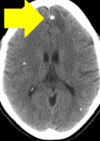

Size of tissue cysts in cysticercosis? where are they found?

A

1-2cm

Muscle (palpable) - eventually form calcified streaks

brain - seizures

7

Q

Most common cause of non-epileptic seizures worldwide

Neurocysticercosis